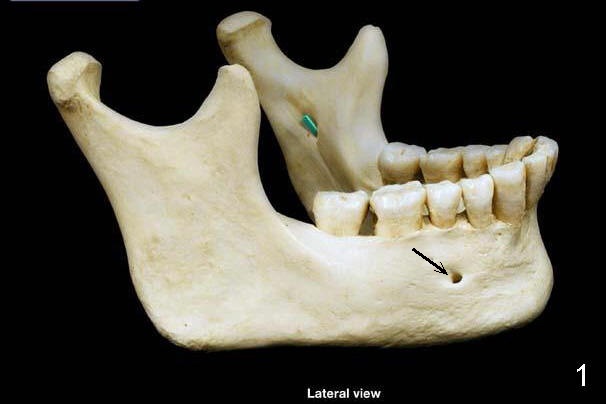

图一显示下颌骨侧面,绿色代表下颌孔,下齿槽神经由此进入,从颏(ke)孔出来(箭头)。颏孔位于第一,第二下前臼齿之间,如果我们拿探针插入颏孔,方向如箭头表示:往前往下,说明颏神经(图二:Mental nerve)却从相反方向出来,颏神经襻由图三Anterior loop of mental nerve表示。颏神经(襻)变异很大(图四红色),颏神经从下齿槽神经(黄色)分出后,后者继续往前行走,成为切牙神经(图四蓝色,图五Incisive nerve),支配下前牙。颏部取骨(Chin block harvesting)可能造成暂时性下前牙感觉减退,或者术中出血,压迫就可以止血。下切牙植牙钻洞可能损伤切牙血管,但是种植体植入后便止血。